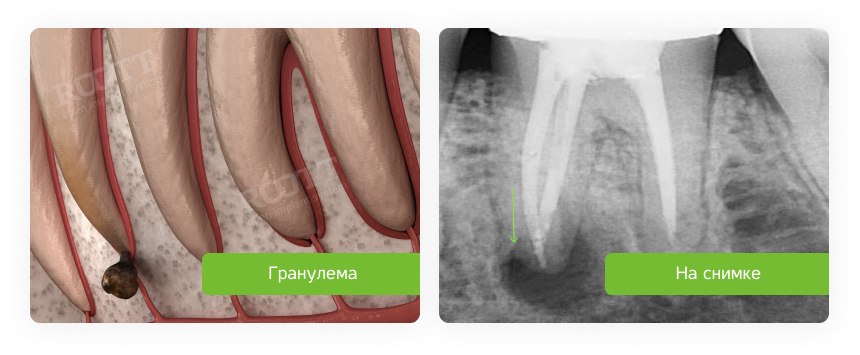

image 17Кб, 300x169

300x169

image 36Кб, 1024x616

1024x616

Сап медач.

Опустились дёсны в нескольких местах, обнажились шейки зубов. Чувствительные, болят от прикосновений, могут реагировать на холодное, горячее, сладкое.

Ситуация как примерно на пик2.